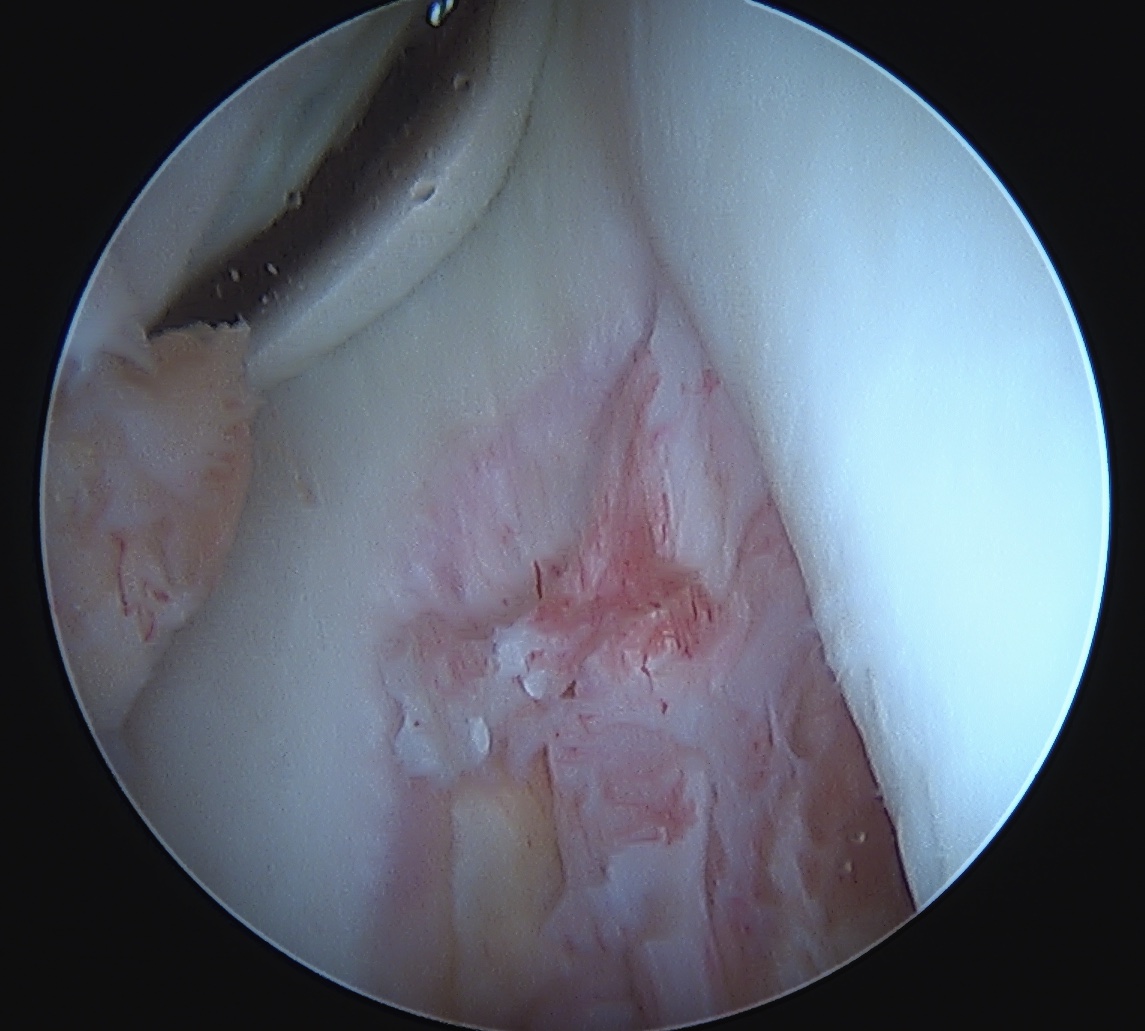

Arthroscopy

May miss tear as is extra-synovial

Acute PCL femoral avulsion

Apparent ACL laxity due to PCL tear and posterior tibial sag; ACL tension restored with anterior drawer